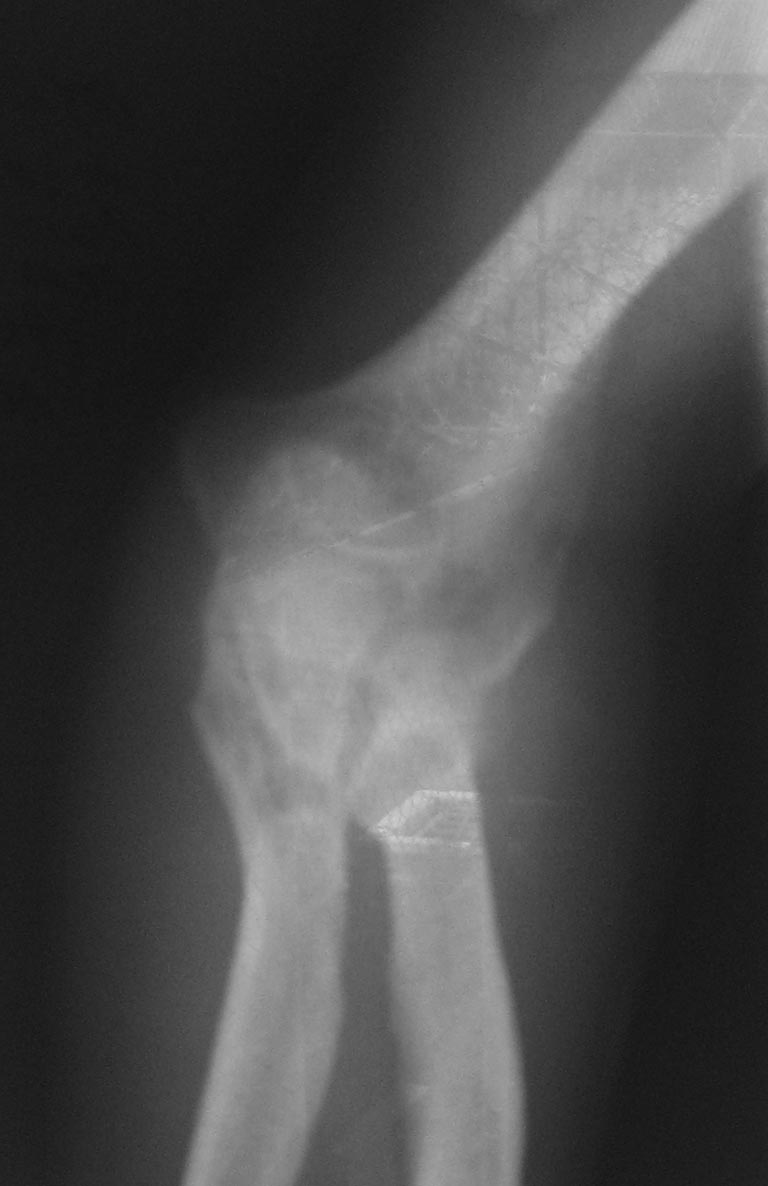

Лечения не было. Сейчас - контрактура и резко выраженный болевой

синдром, в т.ч. вследствие давления trohlea humeri изнутри на кожу. МРТ

или КТ невыполнимо. Тактика?

Имя     : IMG_0297.JPG

Тип     : image/jpeg

Размер  : 67927 байтов

Url     : http://weborto.net:8080/pipermail/ortho/attachments/20141120/eb188f24/attachment-0004.jpeg